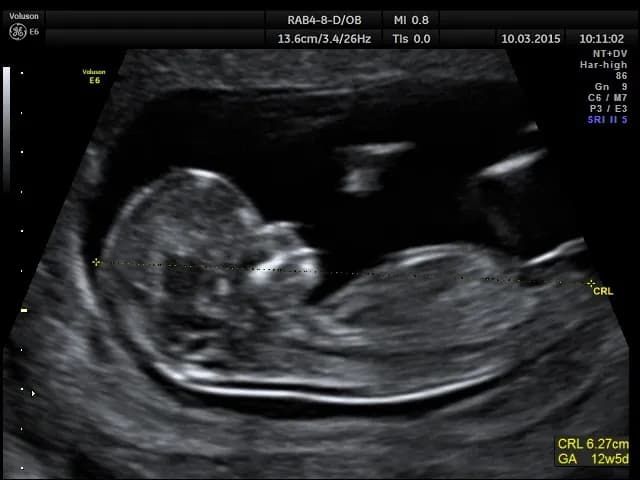

Zastanawiasz się, które badanie prenatalne wybrać? Sprawdź, jakie są różnice między pierwszym badaniem prenatalnym dopochwowo czy przez brzuch.